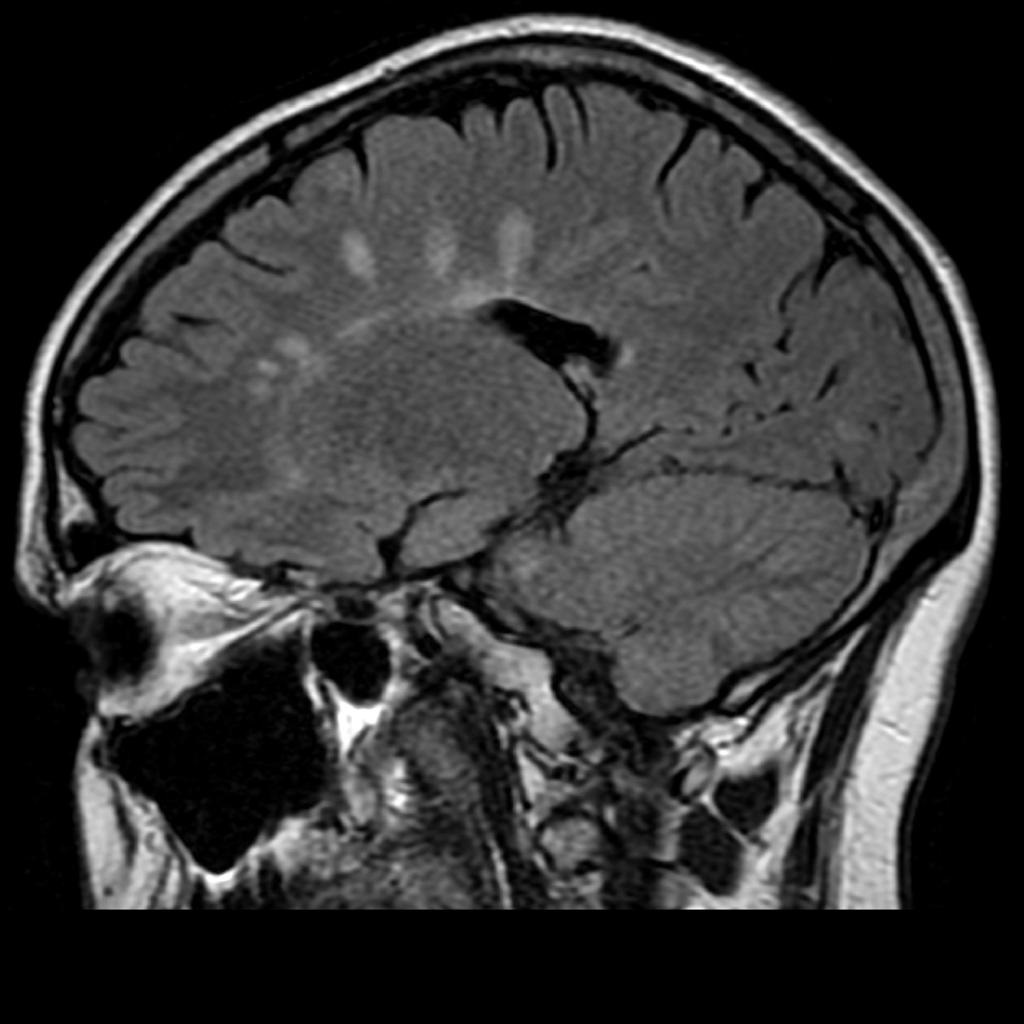

what type of imaging should be used to view demyelinating lesions?

MRI w/ contrast

Will show plaques representing areas of demyelination

MRI showing multiple white matter plaques perpendicular to the corpus callosum --> DAWSONs fingers!